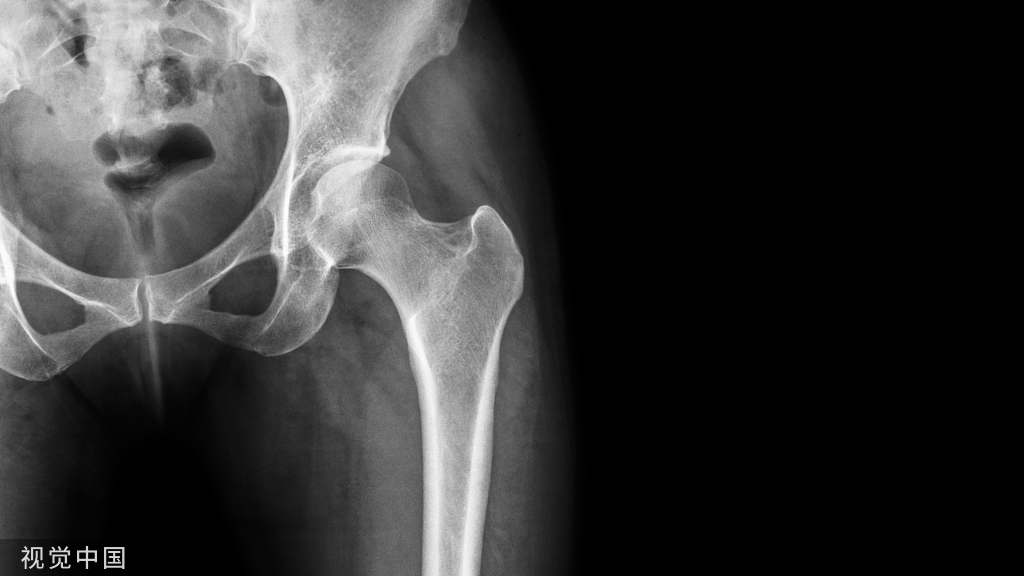

3、股骨颈截骨

脱位髋关节,然后进行股骨颈清理,包括股骨截骨部位。测量股骨头中心至小粗隆的距离(LOC),标记截骨线,一般位于小粗隆上1.5cm左右。

细节:可让助手在对侧进行截骨,这样便于操作,确保截骨面平行。同时注意截骨时避免大粗隆损伤。